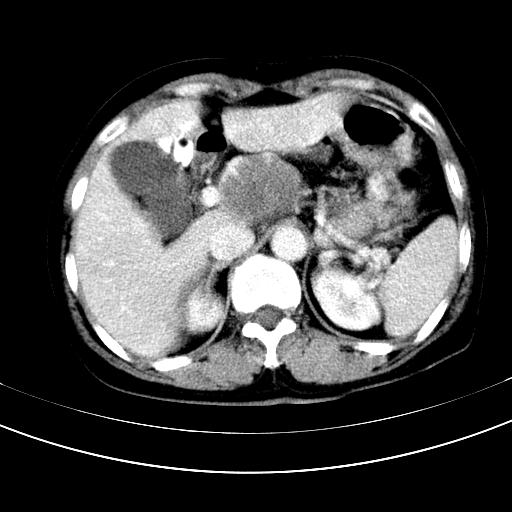

标题: CT12767:肝脏病变请会诊

补充强化片

胃内见充盈缺损,建议行胃镜病理检查,如果胃内无占位,则肝内考虑左叶、尾叶为包膜型肝癌,如有则考虑为转移瘤

胃内的充盈缺损,当时让患者俯卧位在扫描一下就 好了,当然最好是增强扫描,肝脏的病灶平扫很难定性,可以考虑是肝癌·血管瘤·转移瘤!

胃内见充盈缺损,建议行胃镜病理检查,如果胃内无占位,则肝内考虑左叶、尾叶为包膜型肝癌,如有则考虑为转移瘤,左侧肾上腺 明显增大,成结节改变,本人考虑转移瘤可能性大。

胃内的充盈缺损因胃壁不厚,我个人考虑为胃内残留物。肝左叶及尾叶病灶,我首先考虑血管瘤,其次为肝癌。(尾叶的更低密度区太规整)

肝脏左叶和尾叶均见略低密度影,尾叶病变内见坏死?其边界清晰,形态规整1血管瘤,2肝癌待排

胆囊内见一略高密度影,息肉?

1.肝左叶及尾叶占位建议增强2.肝硬化

胃内充盈缺损考虑为胃内存留物,肝左叶和尾状叶两个病灶,均为低密度,建议增强。